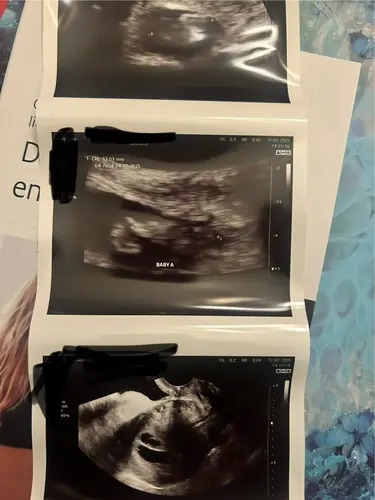

Tweeling! Zo spannend hoe het ontwikkeld de aankomende tijd. ♥️